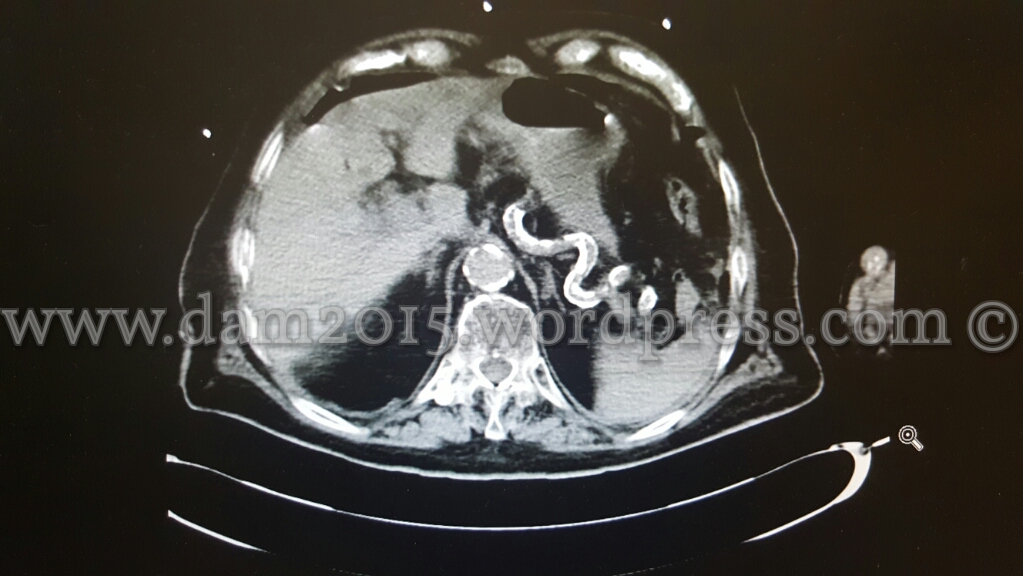

Eseguita TC addome con MDC che mostra aria libera intraperitoneale disposta prevalentemente anteriormente al fegato ed al corpo gastrico, come da perforazione di viscere cavo.

Evidente inoltre marcato ispessimento parietale dell’antro gastrico, della I e II porzione duodenale e del tratto medio-distale dell’esofago (che rimane beante lungo tutto il suo decorso) con edema periviscerale .

Falde di versamento periepatico, tra le anse intestinali, in sede perisplenica e nello scavo pelvico.

Reperto collaterale di marcata calcificazione dei vasi splenici.